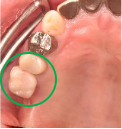

男性 Nさん 70代 (インプラント)

主訴

右下奥の歯が、グラグラして噛むと痛い。

治療内容

歯根の周りの骨が全く無い状態でしたので、保存することができず抜歯しました。3本歯がないところに2本インプラントを埋入しました。

所感

抜歯後、歯がなくなったところを補う方法には、部分入れ歯とインプラントがあります。この症例の場合、右下以外ほとんど歯が残っていますので、もし部分入れ歯にした場合、入れ歯のところで他のところと同じ感覚で噛むことができないので、慣れることが大変です。また部分入れ歯の支えになっている歯に負担がかかりますので、今後さらに歯を失う可能性が大きくなります。インプラントは、自分の歯と同じ感覚で噛むことができ、単独で植立していますので他の歯に負担がかかることがありませんので、更に歯を失うことを防ぎます。

インプラント2本:¥363,000×2本=¥726,000(税込)

ポンティック1本:¥115,500(税込)

合計:¥841,500(税込)

Before

※赤丸を抜歯しました。

After